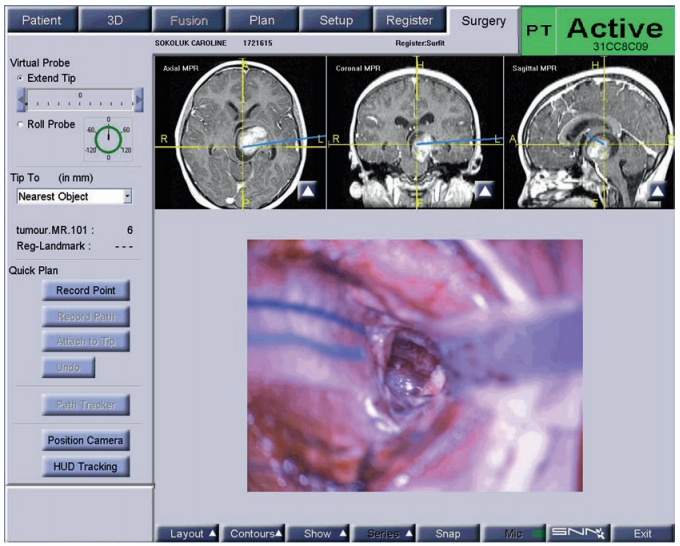

Rutka教授在详细了解Luke的病情和相关资料后表示:他可以为孩子做手术,并且能顺利切除大部分肿瘤,根据术后情况决定是否辅以化疗和具体治疗方案,但暂时不建议放疗。在得到Luke父母的肯定答复后,Rutka教授及其团队很快就为患儿行切除手术。颞部开颅经左侧颞中回入路至病灶处。术中神经导航用于确定肿瘤的边界,用超声刀剥除病变。

Rutka教授认为,在入路和长期治疗方面,局灶性被盖肿瘤对神经外科医生来说是一个较大的挑战。手术入路的选择包括经经外侧裂入路、经颞叶入路或经胼胝体入路,这取决于肿瘤的大小、原发位置及生长形态特点,本次手术教授选择了经颞叶入路。较佳的神经外科切除是通过使用神经导航,特别是磁共振扩散张量成像序列,术中神经导航,术中MRI扫描的辅助,正如他在Luke的手术中所做的那样。

图3。局灶性中脑肿瘤患者的术中导航情况,显示了术中神经导航切除深度和通过颞中回的小手术通路。